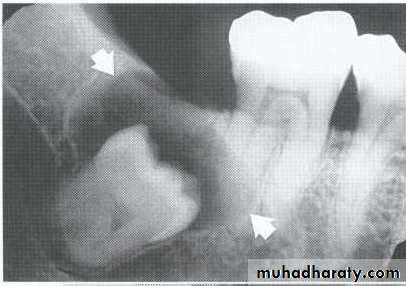

Multilocular appearance, expansion (arrowed) and considerable displacement of the adjacent teeth.

Buccal and lingual expansion (arrowed) and the undulating cortical border.